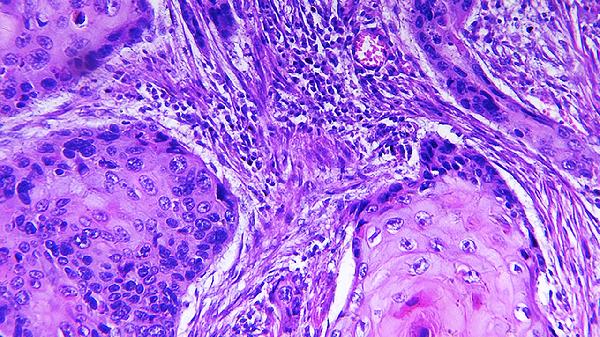

神经性皮炎的种类有很多,但不管是哪种类型的皮炎都会对患者的皮肤造成很大的伤害,此病好发于颈部、四肢、腰骶,不仅对患者的外貌造成影响,长久下去还会造成延误病情,对身体有很大伤害,及时治疗虽然是关键,但是要针对性,找出病因才能对症下药,下面我带大家来了解下,神经性皮炎内外原因有哪些?神经性皮炎为表皮过度角化或角化不全,上皮脚向下延伸,棘皮层以及真皮层增生肥厚,细...